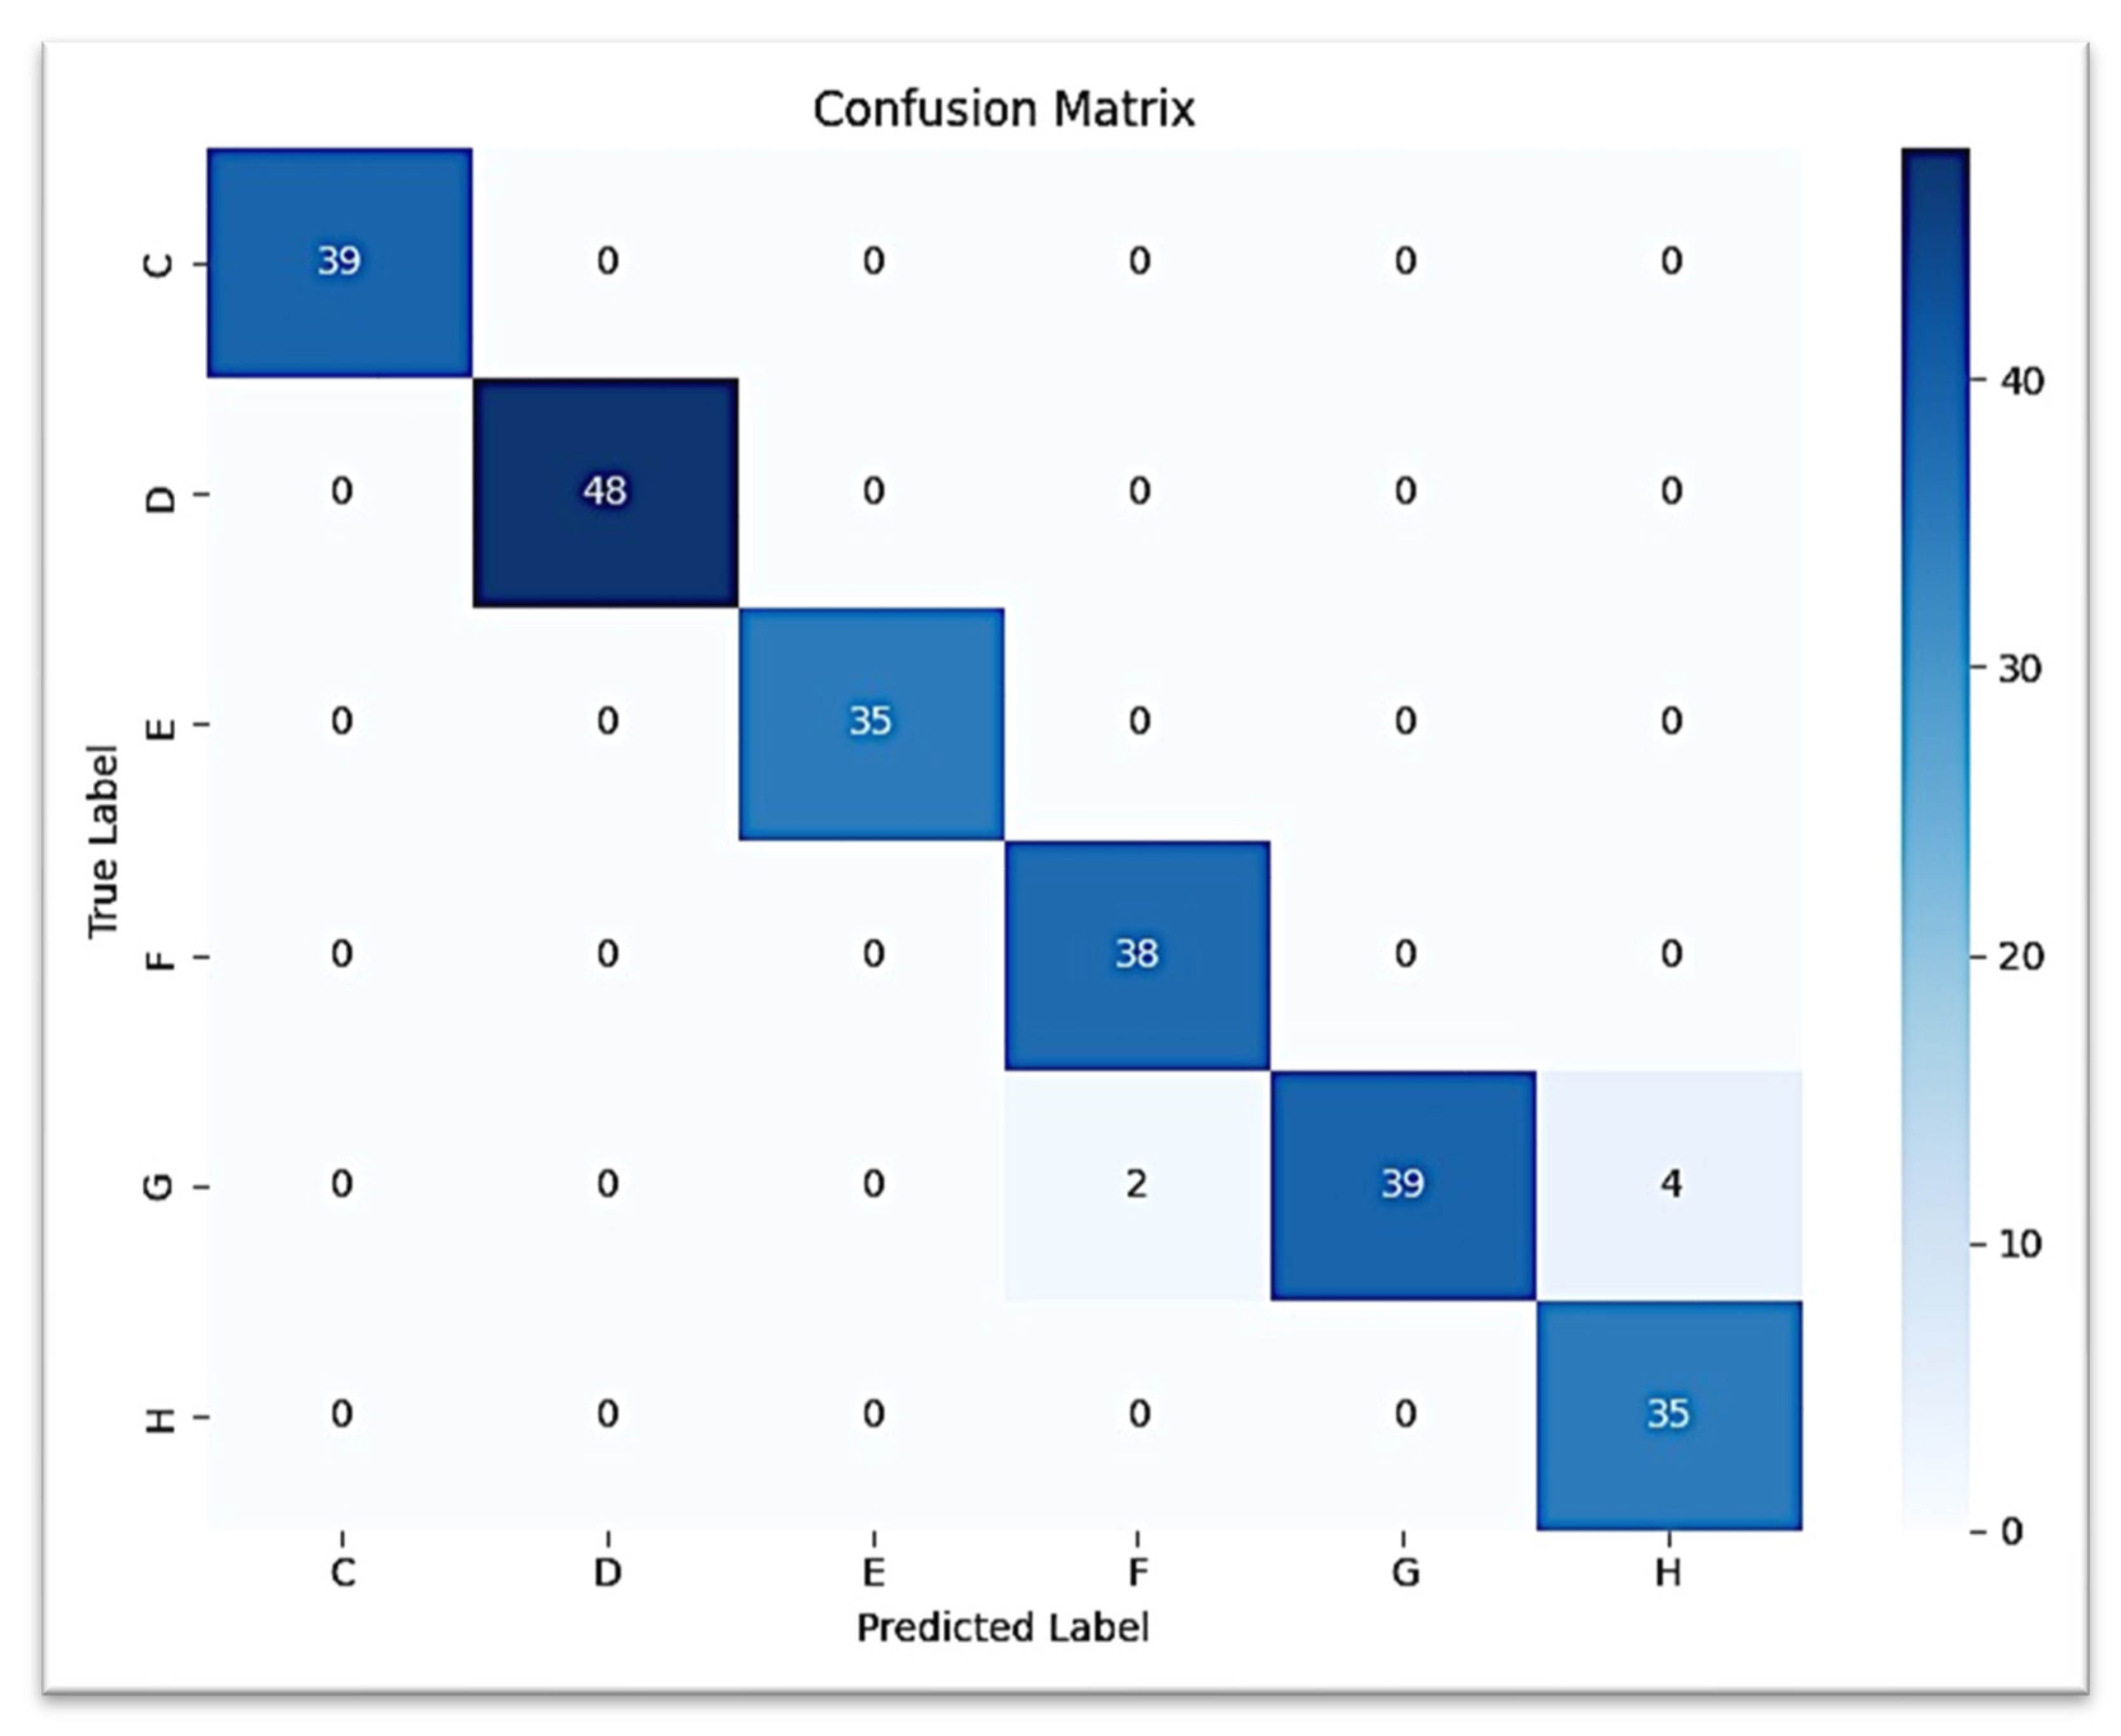

The confusion matrix for canine prediction graphed in

Figure 7 shows that almost all of the strong diagonal elements indicate the correct stage predicted stage. A similar multi-class ROC curve (

Figure 8) suggests that the model is robust to all stages of canine development (AUC = 1.00 for all but G stages, which scored AUC = 0.99).

The second CNN model predicting the development of the lower canine from the second molar ROI provided a test accuracy of 97.50% (0.975 weighted F1-score). Classification was perfect (F1 = 1.00) for stages C, D, and E. Stage F was predicted with high performance (precision = 0.95, recall = 1.00, F1 = 0.97), while stage H had lower precision (0.90) but retained perfect recall. Confusion occurred most often between stage G and stage H, with very few G samples classified as H.